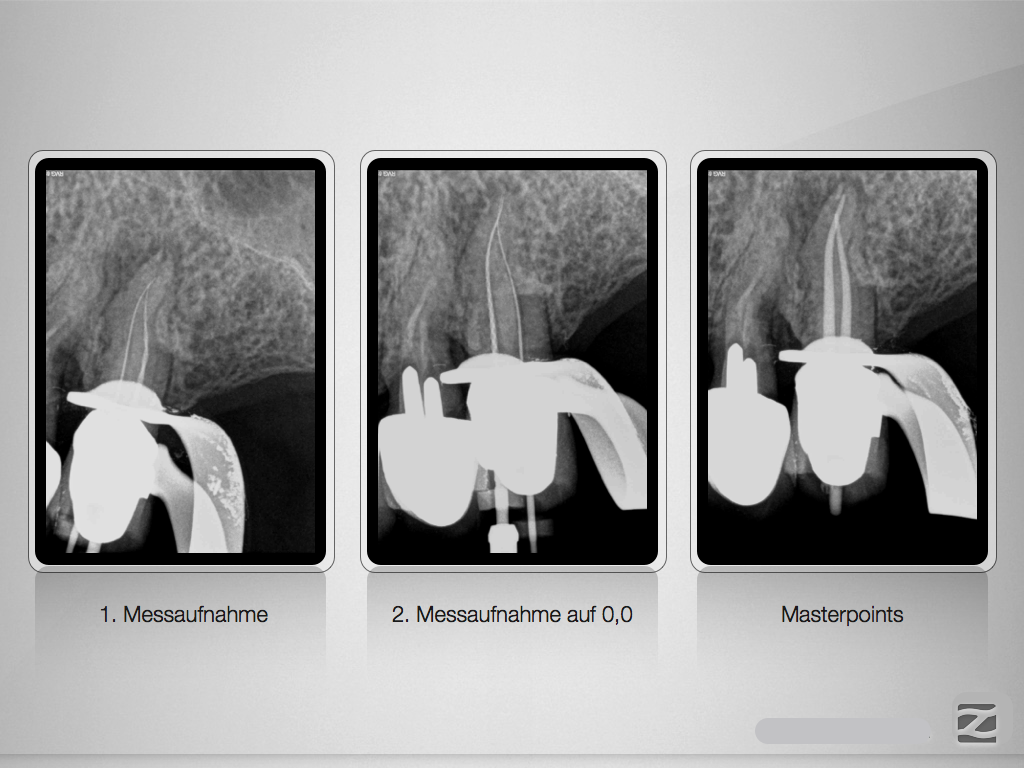

Die Offensichtigkeits-Gefahr